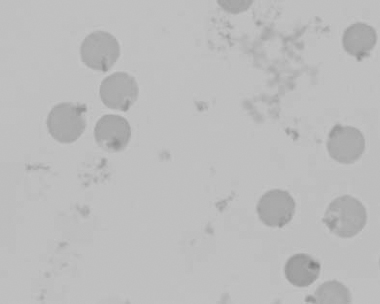

Figure 1.22 New methylene-blue-stained Canine blood film showing reticulocytes (also see color section).

Figure 1.23 Canine blood film showing rouleaux formation (also see color section).